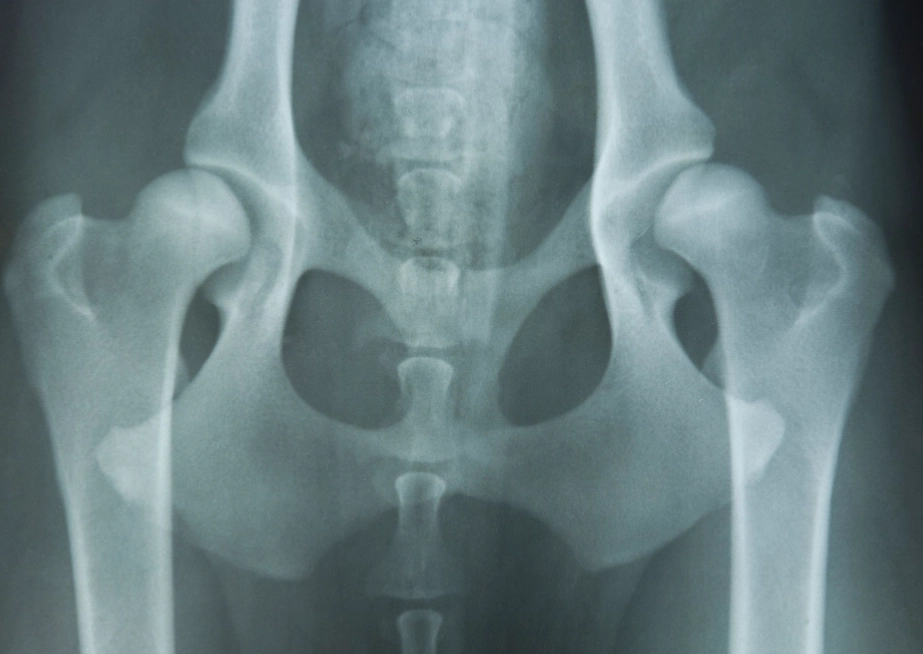

Let's break it down simply. A healthy hip is a ball-and-socket joint that fits together snugly. With hip dysplasia, the socket is too shallow, and the ball (the head of the femur) is loose. This poor fit causes abnormal wear and tear every time the dog moves. It's not just arthritis—arthritis is the result of the instability. The condition is primarily genetic, but factors like rapid growth, improper nutrition, and excessive exercise in puppyhood can worsen it.

- X-Rays (Radiographs): This is the gold standard. But not all X-rays are equal. A quick, awake X-ray often misses the true degree of laxity. For a definitive diagnosis, especially in young dogs, a hip-extended ventrodorsal view and often a PennHIP or Dorsal Acetabular Rim (DAR) view are needed. PennHIP, in particular, can detect laxity in puppies as young as 16 weeks, which is a game-changer for early intervention.

- Sedation: For accurate positioning and to relax the muscles, sedation is usually necessary. Don't skip it—a poor-quality X-ray leads to a poor diagnosis.